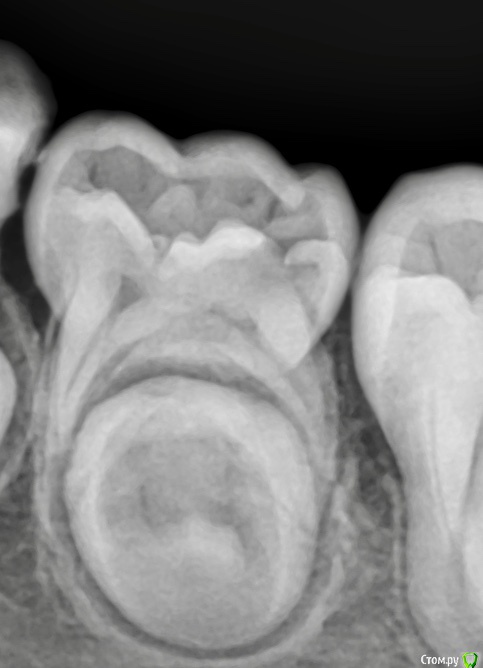

CRAZYDUCK Опубликовано 20 июня, 2018 Автор Поделиться Опубликовано 20 июня, 2018 Мысли вслух Отношение к периодонтитам у меня радикальное . Не было у меня положительных наблюдений. Девочке 4 года , лечение предстоит сложное и длительное . 8.5 зуб разница между первым фото и вторым почти три недели , точка вскрытия указана стрелкой . На момент лечения зуб болит , подвижен. Попытка лечения предпринята - экссудация из корневых каналов бешеная. Удалишь - нужно обязательно сделать распорку ( предотвратить медиальное смещение 6), но можно легко пропустить момент прорезывания 6 и он быстро встанет на место удалённого 8.5. Предпринять попытку лечения - 50/50 успех , заменить кальций даст ребёнок в 4 года .? В общем нет одного решения для всех похожих клинических ситуаций . 84 лечение обратимого пульпита , 8.5 удаление . 1 Ссылка на комментарий

CRAZYDUCK Опубликовано 21 июня, 2018 Автор Поделиться Опубликовано 21 июня, 2018 Я не очень понял, что было сделано с зубом 8.5? Вылечить его реально, периодонтиты у детей заживают очень быстро, быстрее чем у взрослых. Только вот возраст это да это проблема, в 4 года лечить очень тяжело. а я и не написала , что делала -экстирпация , обработка каналов Гх , в такой ситуации начинаю с 5 зуба . Если экссудации из корневых каналов нет ( после мед обработки Каналов), то лечим -кальций в каналах с последующей заменой . Все время пока я лечила 8.4 ( вит ампутацией ) полость 85 быстро заполнилась кровью - это минут 20-30), успех лечения можно ожидать . Все зависит от того , что считать успехом . Несколько лет назад я пробовала лечить периодонтиты , с последующим контролем rvg .максимум год , бывало , что внешне ( состояние десны) было хорошо, а на снимке -резорбция, бывало , что свищи появлялись все равно . Все снимки я не могу показать ( остались на прежней работе и фото я тогда не делала ). Для меня важный критерий- защита зачатка . Есть сомнения во временном - лучше удалить . 1 Ссылка на комментарий